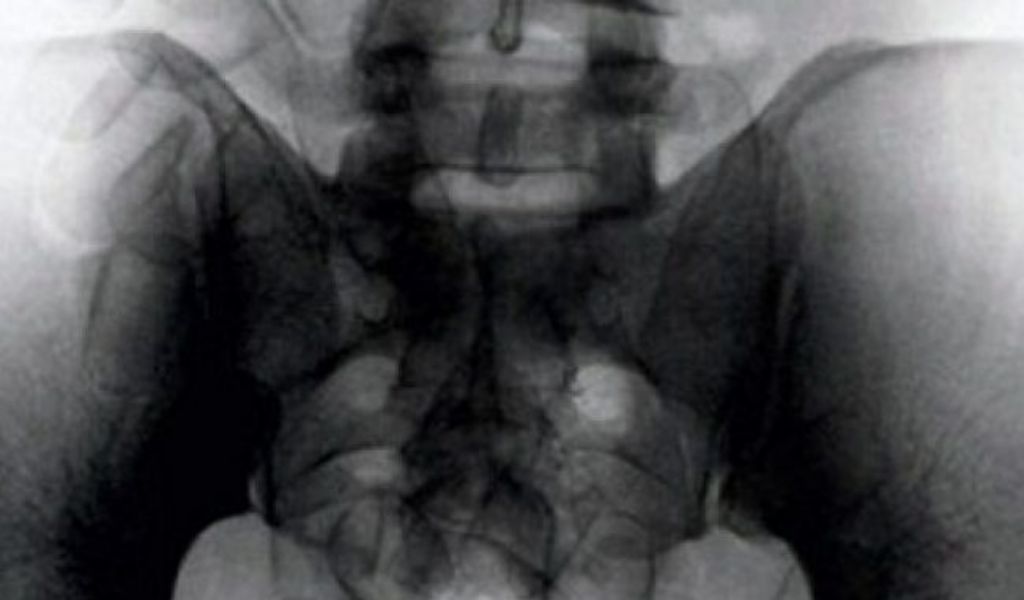

Un cittadino brasiliano è stato trattenuto diverse ore all’aeroporto di Malpensa per una sorta di “malinteso”. L’uomo, che mostrava durante un normale controllo un certo nervosismo e non aveva vestiti in valigia, è stato sottoposto ad un esame più approfondito. La radiografia ha mostrato nel suo intestino quelli che agli agenti, a prima vista, sono sembrati degli ovuli di coca.

Quando, il giorno seguente, il turista si è finalmente “liberato”, ecco la scoperta: non ovuli di cocaina ma dei normali fagioli. Tante scuse e l’uomo è stato lasciato andare.